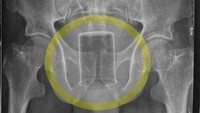

Seorang pria berusia 47 tahun di Nepal pergi ke unit gawat darurat secara tidak sengaja memasukkan gelas ke dalam anus tiga hari sebelumnya. Ia tidak bisa buang air besar dan mengaku memasukkan gelas tersebut ketika mabuk. (Foto: Journal of Nepal Medication Association)